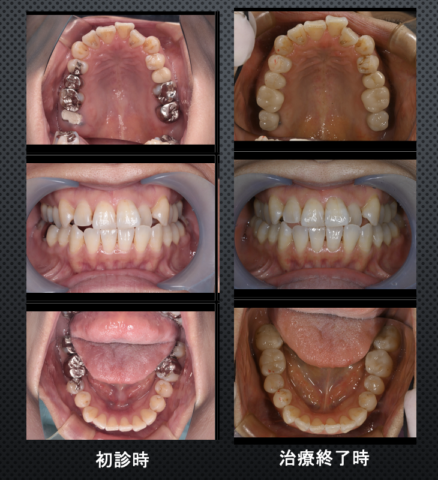

治療前後比較

before

after